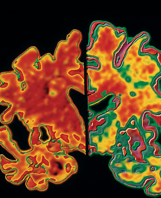

Cancer Drug Shows Promise for Alzheimer's

Neuroscientists at Case Western Reserve University's School of Medicine have made a dramatic breakthrough in their efforts to find a cure for Alzheimer's disease. The researchers' findings, published in the journal Science, show that use of a drug in mice appears to reverse the pathological, cognitive and memory deficits caused by the onset of Alzheimer's. The results point to the significant potential that the medication, bexarotene, has to help the roughly 5.4 million Americans suffering from the progressive brain disease. Read more

Professor Landreth and his research team appreciate the great interest inspired by their findings, but emphasize that clinical trials have not begun or been scheduled relating to this medication.